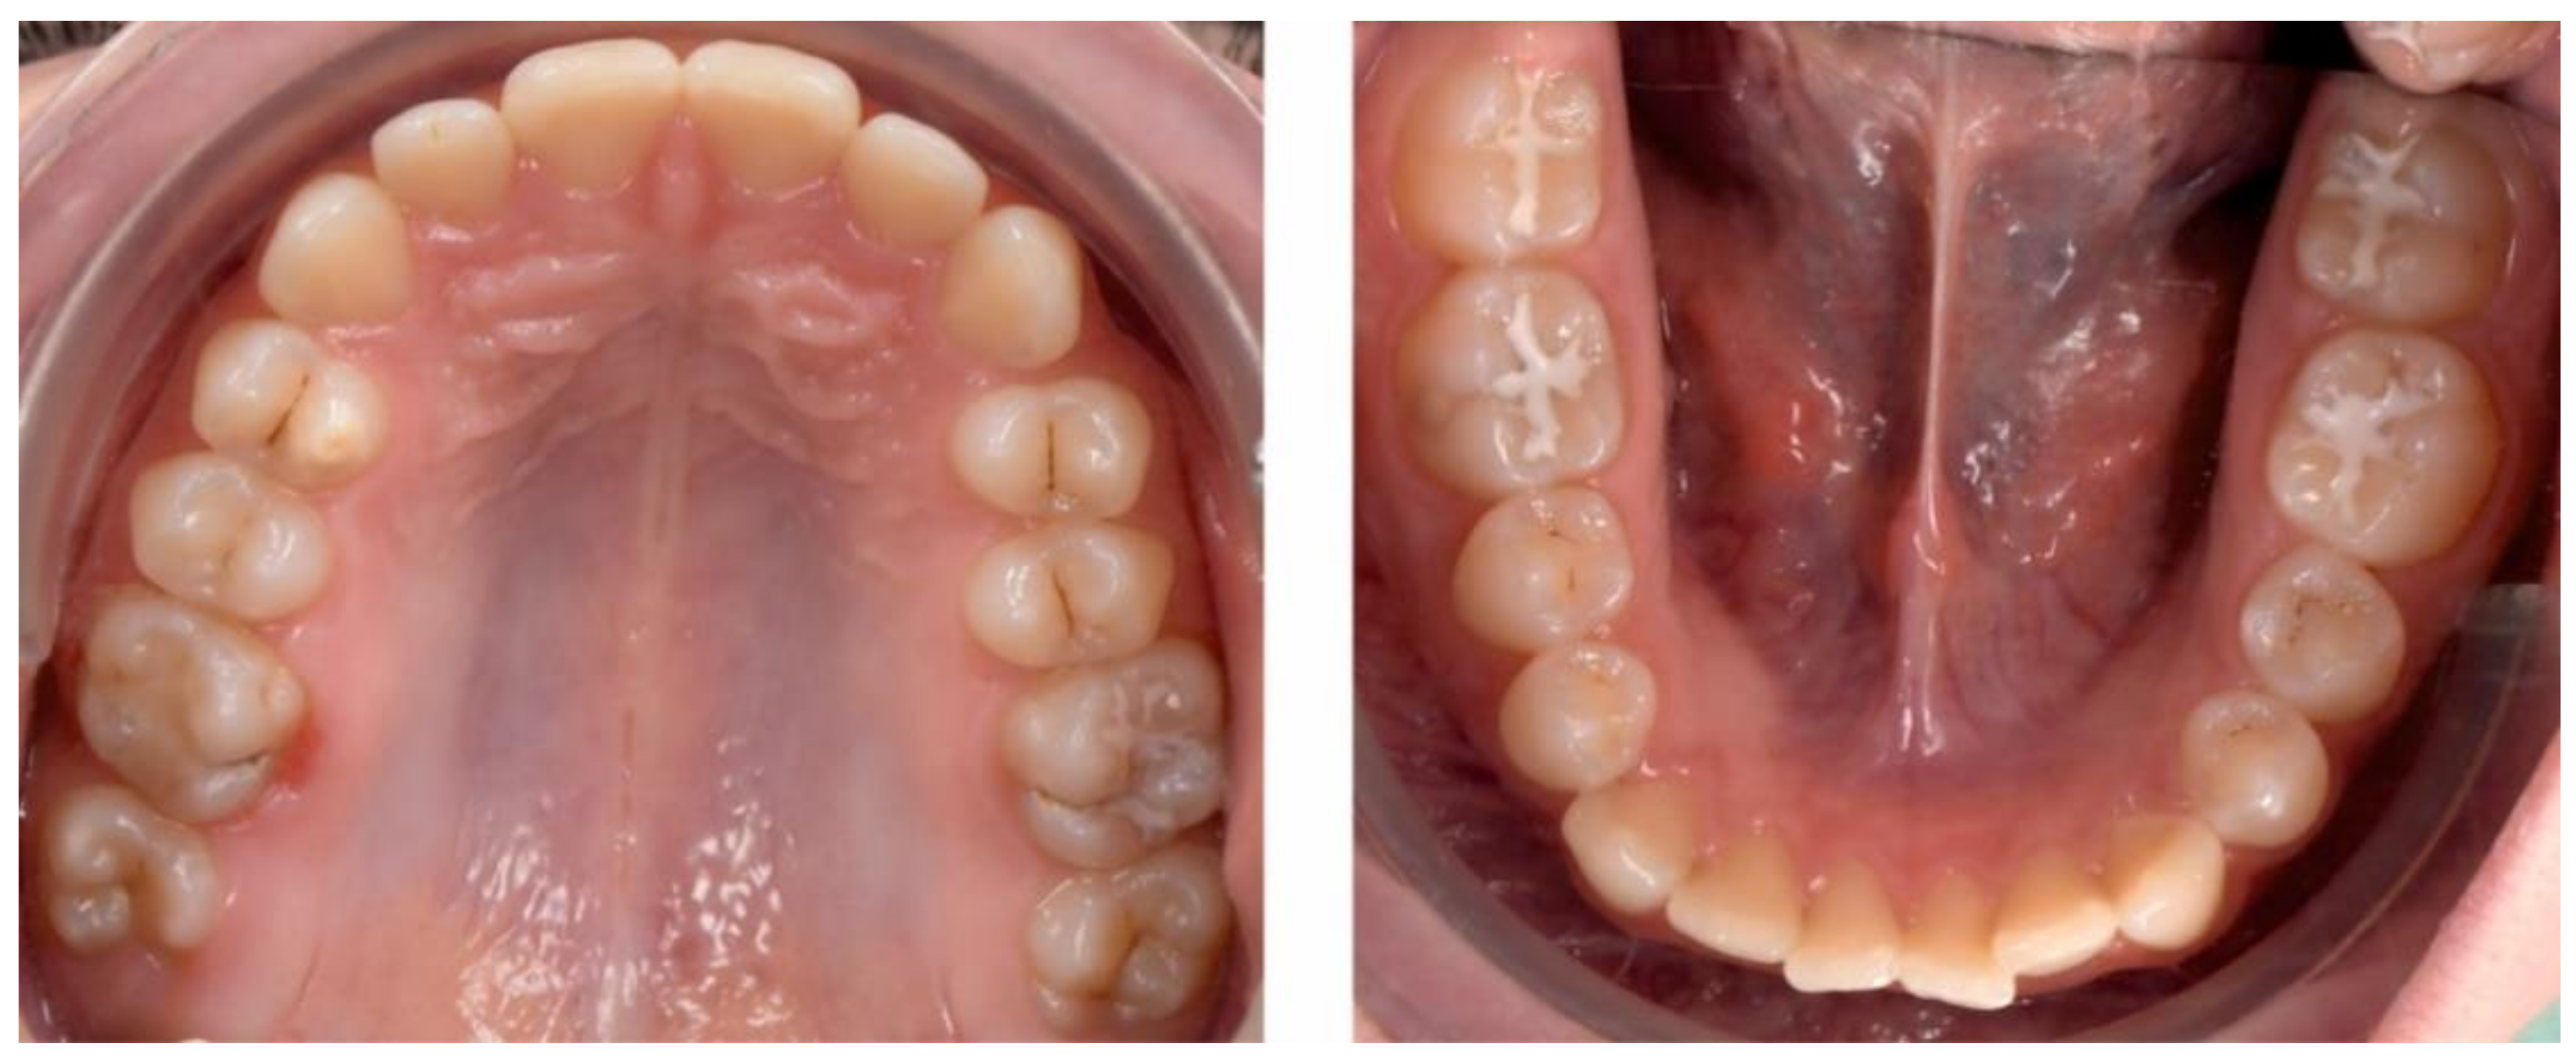

2.2.1. Initial Examination

2.3.2. Second Phase of Treatment—2017—Bite-Blocks and Transpalatal Arch